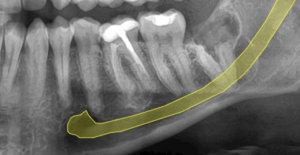

Radiografía postoperatoria inmediata a la coronectomia (extracción de la corona) de tercer molar.